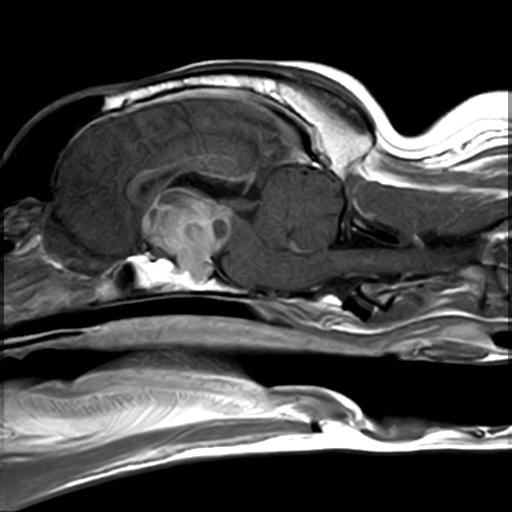

MRI画像:クッシング症候群の犬の下垂体腺腫

上記のような症状が認められた場合、まず血液検査・腹部X線検査などにより、除外診断を行います。臨床症状を含め、特徴的な所見が認められた場合、クッシング症候群の確定診断のためACTH負荷試験と呼ばれる検査を行います。状況により、エコー検査、CT/MRI検査を行い、コルチゾール分泌に関わる下垂体や副腎の状態を確認します。クッシング症候群と診断された場合は、お薬によるコントロール、原因によっては外科手術などが必要となってきます。